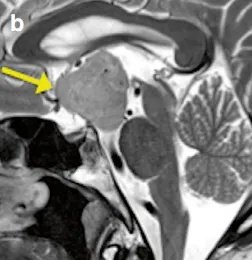

但是医生让我做头部检查,直到我做了MRI检查,答案才残酷地摆在面前:我的脑子里长了一个肿瘤。医生指着MRI图像(图a、b)告诉我,这个鞍上肿瘤已经压迫到了关键的大脑区域——向脚间池延伸并致中脑大脑脚受压变形。